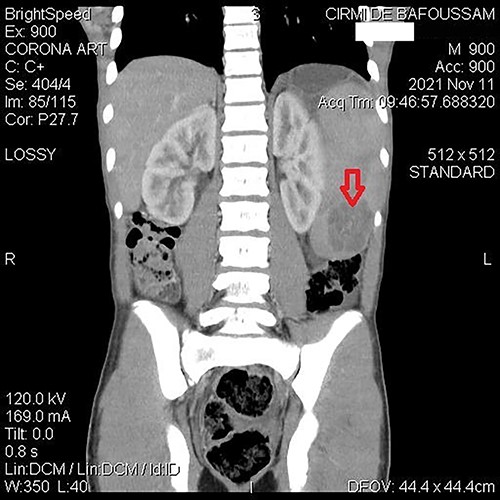

A 15-year-old patient presented with a 3-week history of left upper quadrant abdominal pain with no other symptoms. He had no prior history of pulmonary TB. His vital signs were as follows: temperature = 37°C, blood pressure = 120/78 mmHg, pulse = 84/min, respiratory rate = 15/min, SpO2 = 96% on room air; and physical examination only revealed a mild tenderness in the left upper quadrant with the tip of the spleen expanding to the umbilicus. An abdominal ultrasound (US) followed by a computed tomography (CT) scan revealed a heterogeneous splenomegaly with multiple cystic masses in the spleen and the tail of the pancreas (Figs 1 and 2). Laboratory exams showed a white cell count of 2600/mm3, hemoglobin of 11.4 g/dl, C-reactive protein (CRP) of 34 mg/l, hemoglobin electrophoresis AA and negative malaria and HIV tests. We suspected a primary or secondary malignancy of the spleen, like a lymphoma or a metastatic pancreatic carcinoma. The other diagnoses were tropical splenomegaly and splenic infarct. We performed a distal pancreatectomy with splenectomy, and histopathological analysis revealed caseating granulomas of the spleen (Fig. 3) with no malignancy suggesting TB. Further, a Ziehl-Neelsen stain of the specimen showed acid fast bacilli (AFB). The patient received anti-TB drugs, had an uneventful post-operative course and was discharged on post-operative day 7. On the first month follow-up visit, he reported marked improvement of his symptoms.

Abdominal CT demonstrating a contrast-enhanced hypodense mass in the spleen.